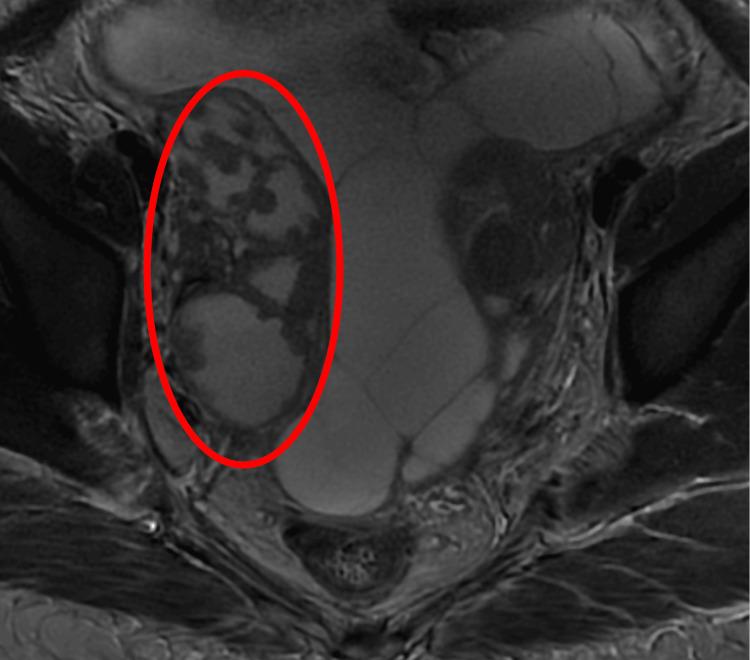

Tuberculosis (TB) is caused by . It is a multisystem infection, but the most common manifestation is pulmonary. TB is the leading cause of death among infectious diseases. Abdominal TB is a form of extrapulmonary TB (EPTB) that often presents nonspecifically and can result from genitourinary or hematogenous spread. We present the case of a 20-year-old Bangladeshi woman who presented with a two-month history of fever and night sweats accompanied by vomiting, tachycardia, and tachypnea. Laboratory investigations revealed elevated inflammatory markers, lactate dehydrogenase, and cancer antigen 125. QuantiFERON-TB (QIAGEN N.V., Venlo, Netherlands) was positive. An abdominal ultrasound showed free fluid throughout the abdomen. A CT scan of the abdomen revealed thickening and enhancement of the peritoneum, omental caking, and bilateral bulky ovaries measuring up to 8.5 x 5.4 cm on the right side, raising suspicion of malignancy. However, an MRI showed that the pelvic masses were, in fact, bilateral hydrosalpinx. Peritoneal analysis indicated a serum ascites albumin gradient (SAAG) of less than 1.1, suggesting peritonitis with neutrophil predominance. Acid-fast bacillus (AFB) culture of the peritoneal fluid grew . Abdominal TB and ovarian cancers can overlap in clinical presentation, especially in young female patients. Imaging may be misleading, as seen in this case. Imaging modalities may assist in the diagnosis; further exploration, particularly diagnostic laparoscopy with biopsy, is required for suspected ovarian cancer and EPTB.

结核病(TB)由……引起。它是一种多系统感染,但最常见的表现是肺部感染。结核病是传染病中主要的死亡原因。腹部结核是肺外结核(EPTB)的一种形式,通常表现不具特异性,可由泌尿生殖系统或血行播散引起。我们报告一例20岁孟加拉国女性病例,该患者有两个月发热、盗汗病史,伴有呕吐、心动过速和呼吸急促。实验室检查显示炎症标志物、乳酸脱氢酶和癌抗原125升高。结核菌素定量检测(QIAGEN N.V.,荷兰芬洛)呈阳性。腹部超声显示全腹有游离液体。腹部CT扫描显示腹膜增厚、强化,网膜饼状增厚,双侧卵巢肿大,右侧最大径达8.5×5.4cm,怀疑为恶性肿瘤。然而,磁共振成像显示盆腔肿块实际上是双侧输卵管积水。腹膜分析显示血清腹水白蛋白梯度(SAAG)小于1.1,提示以中性粒细胞为主的腹膜炎。腹膜液抗酸杆菌(AFB)培养长出……。腹部结核和卵巢癌在临床表现上可能重叠,尤其是在年轻女性患者中。如本病例所示,影像学检查可能会产生误导。影像学检查方式可能有助于诊断;对于疑似卵巢癌和EPTB,需要进一步检查,特别是诊断性腹腔镜检查及活检。